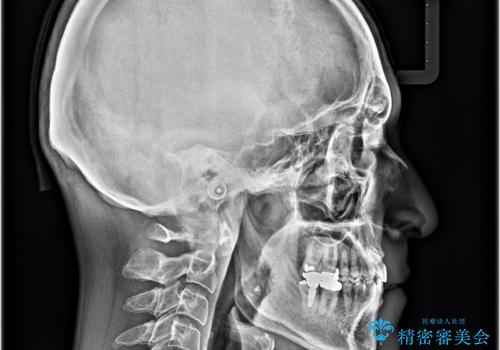

受け口を治す ワイヤー装置での矯正治療

- 上下前歯の反対咬合と左下奥歯の痛みを気にして来院された患者様です。

歯並びや口元の印象、奥歯の咬み合わせから、非抜歯にて矯正治療を行うこととしました。

また、左下の奥歯は親知らずの影響で手前の歯の歯根までむし歯になってしまったため、親知らずとともに抜歯をし、インプラントによる補綴治療を行うこととしました。

矯正治療は、ワイヤー装置とマウスピース矯正との選択肢がありましたが、マウスピース矯正は自己管理が煩わしいことを気にされて、目立たないワイヤー装置にて行うこととしました。